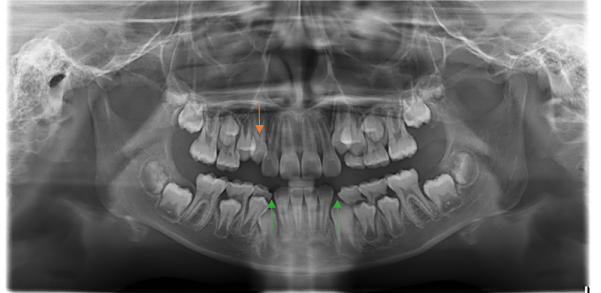

レントゲン写真

右上の犬歯(向かって左、オレンジの○と↓の歯)が上の方から生えてきたために、X線撮影などの検査を行いました。X線によると下の犬歯(緑の↑)部も放出のスペースがなく、八重歯になりそうでした。